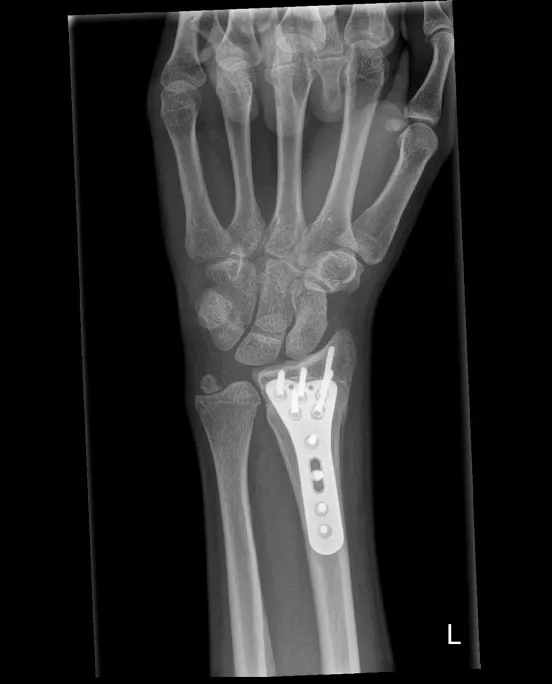

Operatief

Indien de breuk verplaatst is of onvoldoende stabiel:

- Pinnen (Kapandji-techniek): metalen pinnetjes door de huid, blijven 6 weken; risico op lichte inzakking

- Plaat en schroeven: meest gebruikte techniek; geeft meer stabiliteit en kortere gipsperiode; plaatje hoeft meestal niet verwijderd te worden

- Externe fixator: uitwendig frame, gebruikt bij open breuken

Alle ingrepen gebeuren via het chirurgisch dagziekenhuis, meestal onder plexusverdoving.